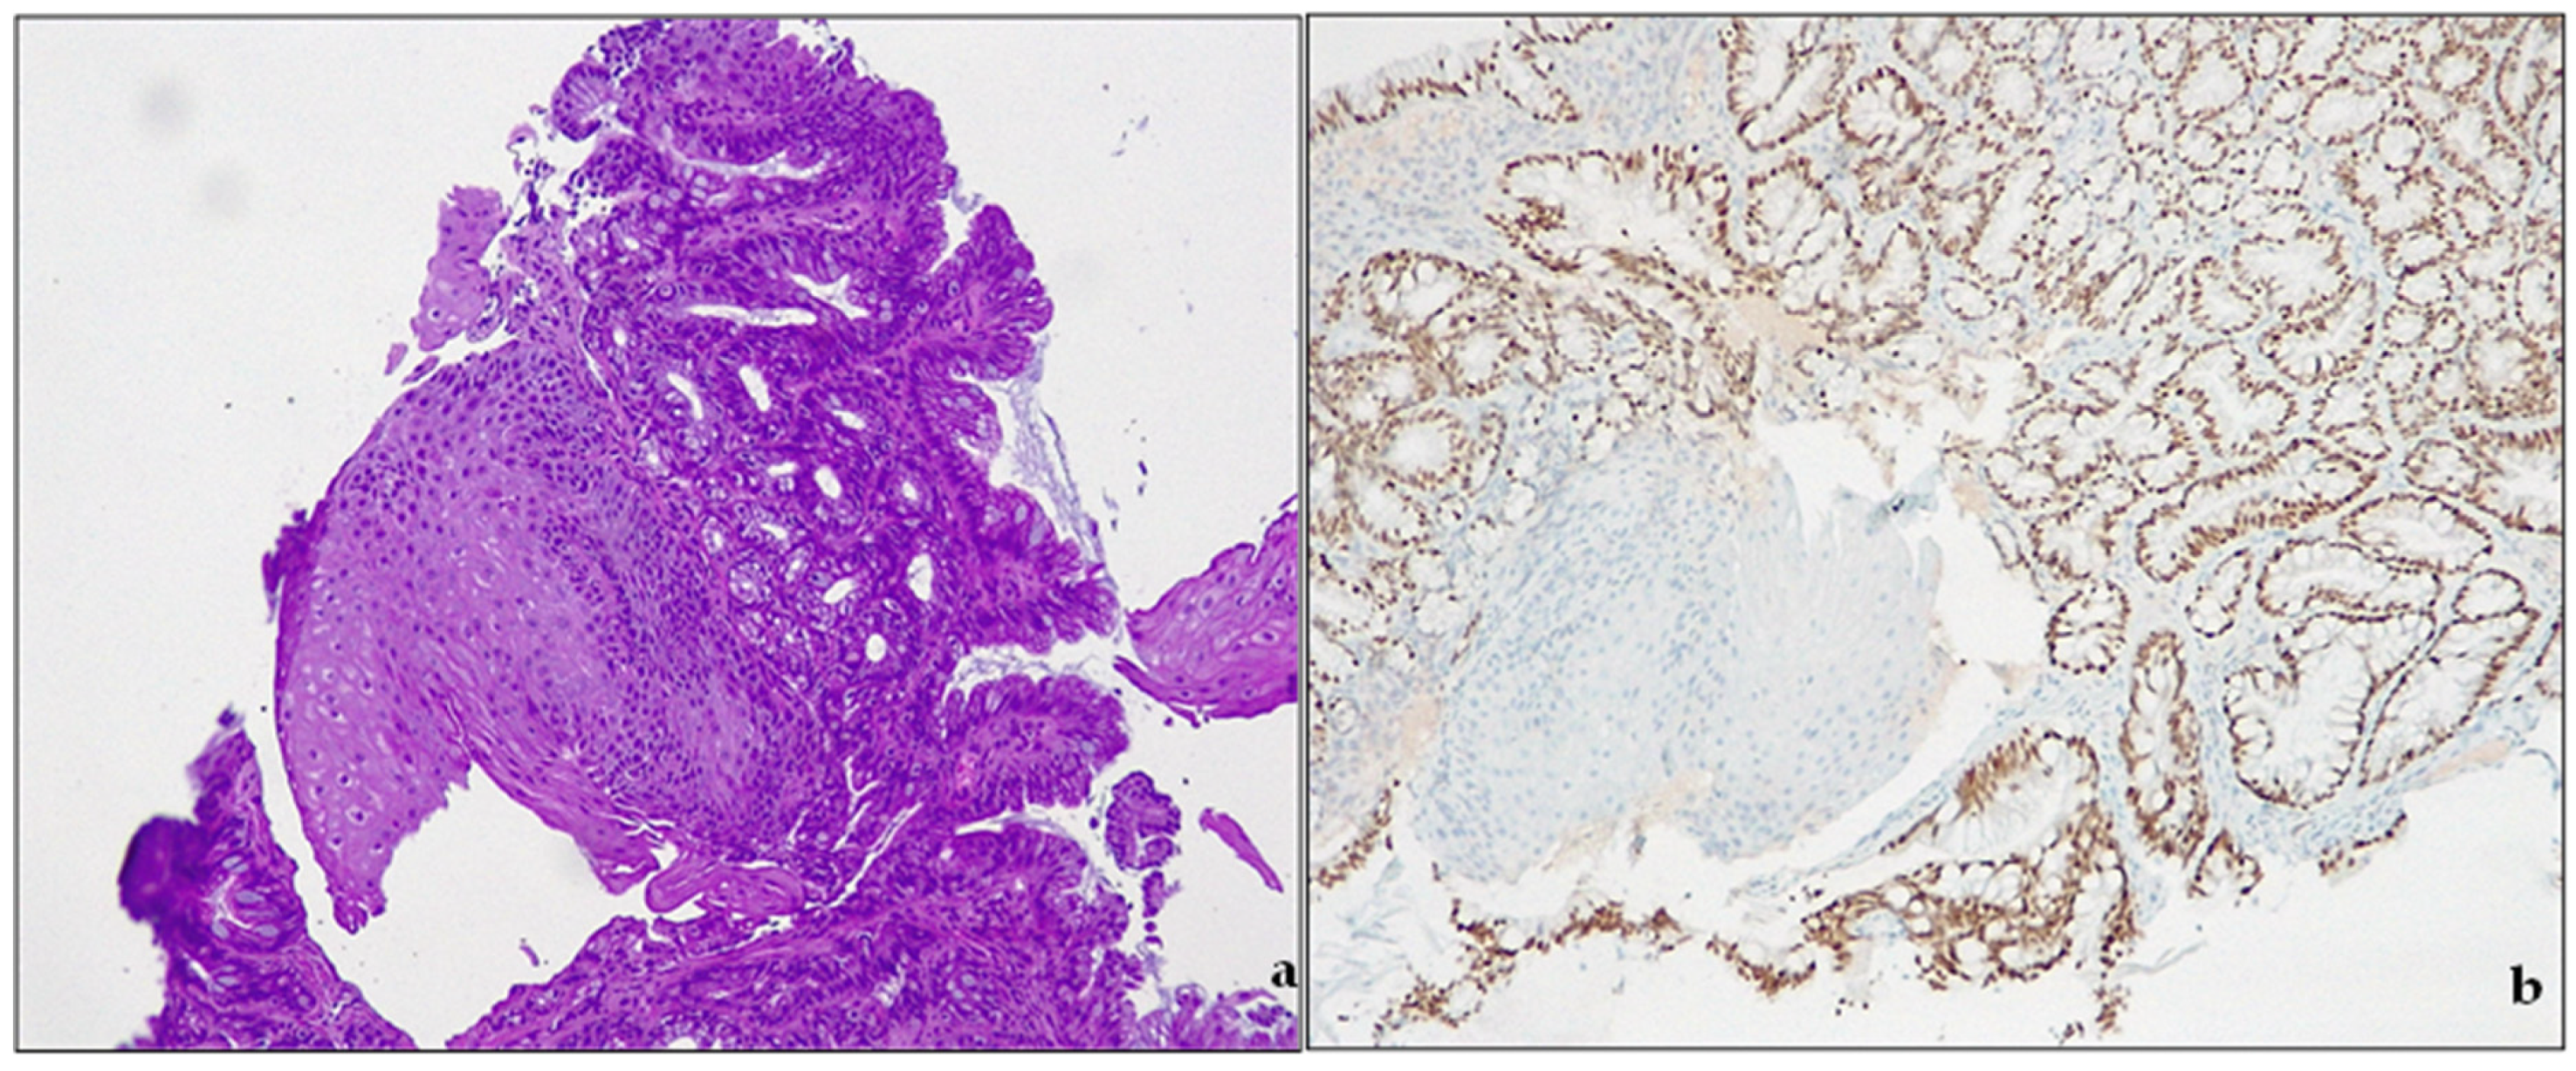

Figure 3.

Barrett’s esophagus. (a) intestinal metaplasia. H&E, original magnification 100×; (b) CDX2 expression, original magnification 100×.